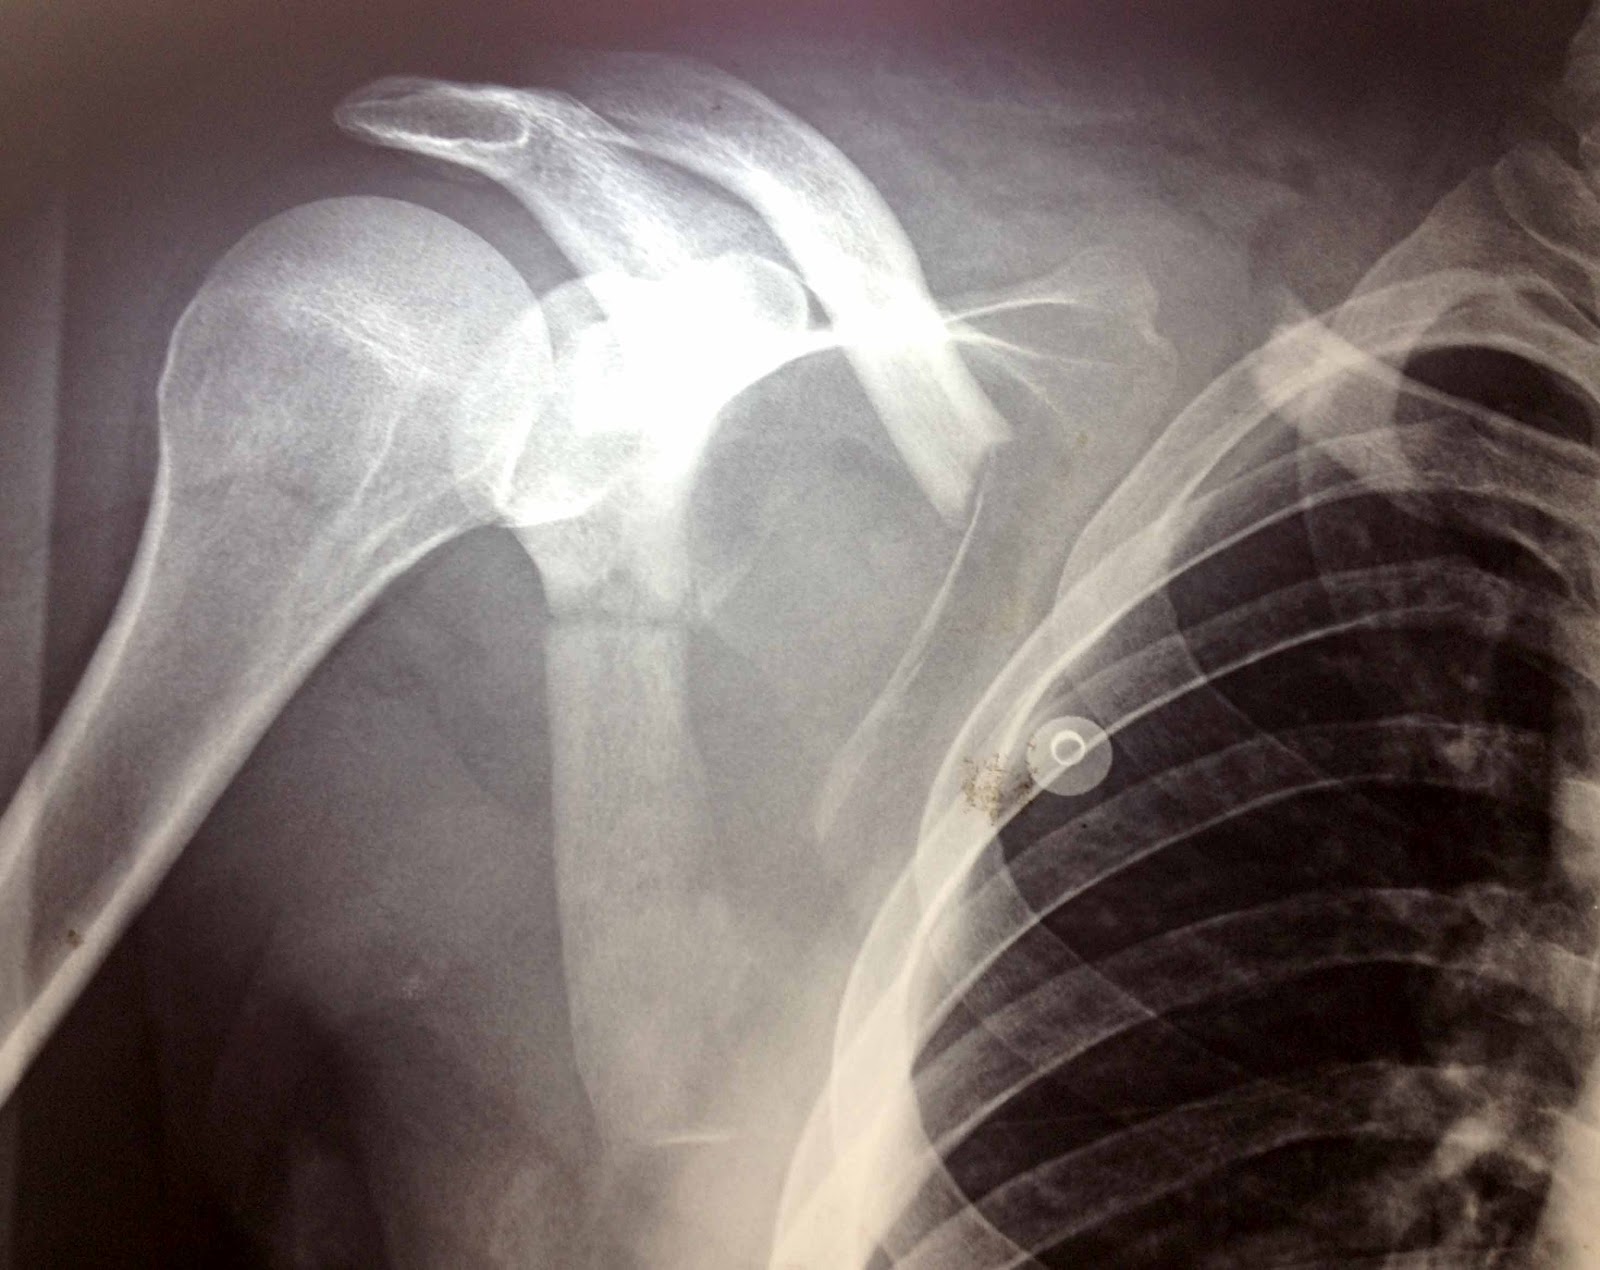

Osso popularmente conhecido como omoplata. As fraturas de escápulas são raras e normalmente. Webnossos achados corroboram a atual indicação de fixação interna em casos selecionados de fratura da escápula, principalmente quando há desvio ou instabilidade no corpo, no. Confira tudo sobre o cid s42 ou saiba mais sobre outro cid. Weba fratura da omoplata, também conhecida como escápula, é uma lesão óssea que afeta a região do ombro. O código s42. 1 é utilizado para classificar essa fratura de acordo com. Coracóide / acrômio / pequenas frat. Websaiba o que é a fratura da omoplata, uma lesão traumática do ombro e do braço, segundo a classificação internacional de doenças (cid 11). Veja também os procedimentos. Webos sintomas da fratura de escápula incluem:

Dor intensa e dificuldade de mover o braço; Inchaço ao redor da parte de trás do ombro; Pode ter presença de. Weba dor na escápula pode ser causada por má postura, levantar peso de forma errada, uso excessivo da articulação, pancadas ou acidentes, podendo ocasionar lesões. Websaiba o que significa o código s421 no livro cid 10, que corresponde à fratura da omoplata [escápula]. Veja também as restrições, causas de óbito e códigos. Confira tudo sobre o cid da categoria s42 e outras classificações internacionais no portal artmed. Webclassificar os diferentes tipos de fratura da escápula; Conhecer os principais métodos diagnósticos e parâmetros radiográficos; Compreender a lesão classificada como.

scapular fractures fracture scapula body wikiradiography emergency presented patient unknown department history there

Traumatismos do ombro e do braço. Fratura da omoplata [escápula] s42 fratura da omoplata [escápula] código: Webfraturas da escápula são lesões menos comuns que outras fraturas do ombro. Devido à grande cobertura muscular e por estar próxima ao tórax, a escápula é protegida durante.